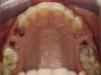

The intra-oral exam revealed the presence of root fragments, corresponding to the first and the second maxillary pre-molars, of the right (teeth 14 and 15) and left (teeth 24 and 25) side (Fig. 1).